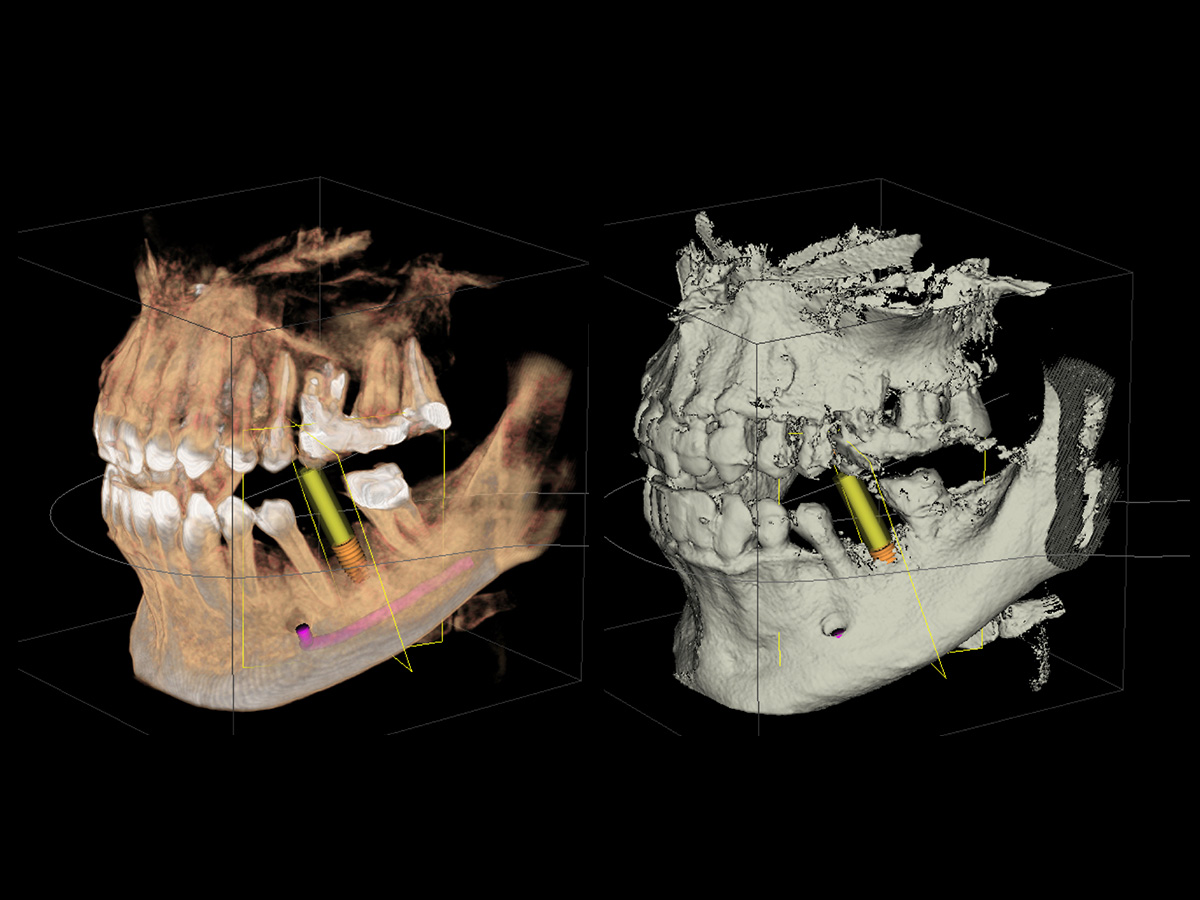

Bei diesem Fall handelt es sich um ein Standardproblem aus dem Patientenklientel von PD Dr. Michael Weinländer. Auf den DVT-Bildern ist ein fehlender Molar mit einer Atrophie der bukkalen Knochenwand zu sehen, was sowohl in der volumetrischen Darstellung (Abb. 1) als auch der Oberflächendarstellung (Abb. 2) gut zu erkennen ist.

Einen horizontalen Schnitt durch die entsprechende Knochenregion mit den gemessenen Knochenbreiten zeigt Abb. 3, während Abb. 4 die geplante Implantatgröße mit den Knochenbreiten im zervikalen Anteil des Kieferkammes abbildet.

Abbildung 1

Ausgangssituation (DVT-Bilder): Fehlender Molar mit Atrophie der bukkalen Knochenwand.

Abbildung 2

Geplante Implantatgröße mit Knochenbreiten im zervikalen Anteil des Kieferkammes.

Abbildung 4